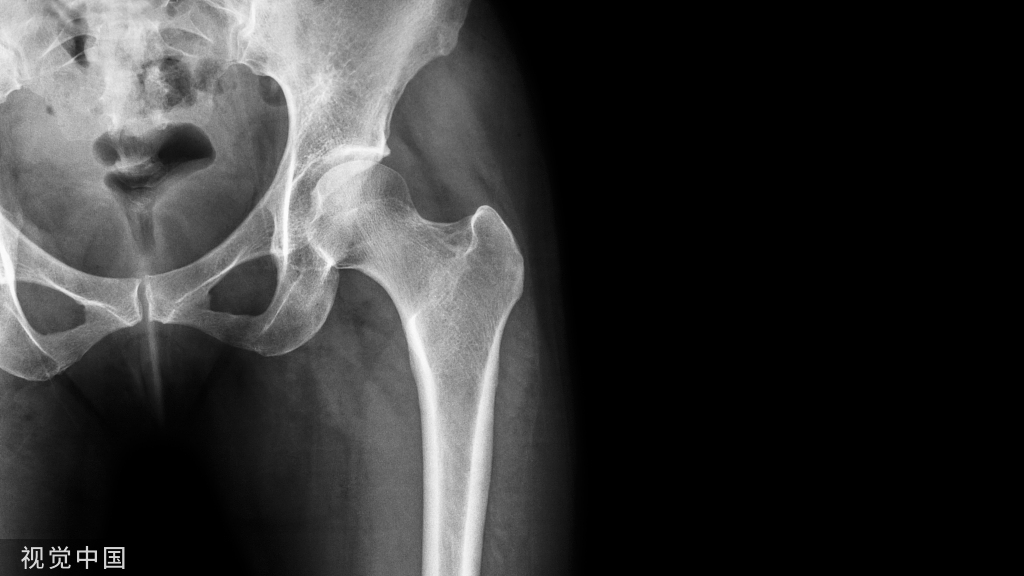

全面的髋关节体检需要通过多个姿势评估髋关节的活动范围、强度,以及进行疼痛激惹测试。基于个体敏感性和特异性的各不相同,为了准确判断FAIS和盂唇病理,结合体检检查是必要的。诊断髋关节微不稳需要提高对患者的怀疑水平,但对微不稳的激惹试验有高度特异性。

确诊髋部疼痛的病因可能具有一定的挑战性,体格检查是明确诊断的基本功。本综述对最新的髋关节体格检查,尤其是与股髋撞击综合征(femoroacetabular impingement syndrome, FAIS)、盂唇损伤(labral injury)及髋关节微不稳(hip microinstability)诊断相关的文献进行了总结。